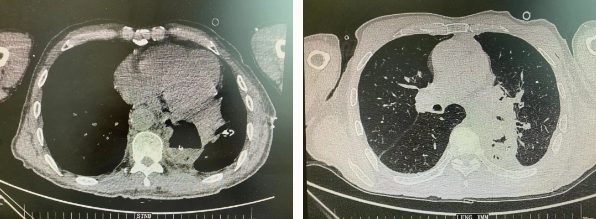

患者王某不幸同時(shí)患食管癌與左肺癌,病理類(lèi)型系雙源發(fā)腫瘤,食管為鱗癌、肺為腺癌。食管癌和肺癌為胸外科最常見(jiàn)的疾病,但同時(shí)患兩種疾病,十分罕見(jiàn)。家屬輾轉(zhuǎn)多個(gè)醫(yī)院,得知李小飛院長(zhǎng)擅長(zhǎng)胸外科復(fù)雜手術(shù),慕名來(lái)西安國(guó)際醫(yī)學(xué)中心醫(yī)院。

經(jīng)過(guò)李小飛教授、李文海副教授、穆強(qiáng)副主任醫(yī)師團(tuán)隊(duì)積極準(zhǔn)備,排除手術(shù)禁忌;經(jīng)過(guò)全科術(shù)前充分討論,大家認(rèn)為:如果分兩次進(jìn)行手術(shù),另一種疾病勢(shì)必會(huì)受到影響,腫瘤可能進(jìn)展。胸外科手術(shù)對(duì)呼吸循環(huán)影響較大,同期實(shí)施兩個(gè)手術(shù)更要小心謹(jǐn)慎。李小飛教授主持術(shù)前討論,設(shè)計(jì)合理手術(shù)方式,由于食管癌胸腔鏡手術(shù)為右側(cè)入路,但為兼顧左肺癌手術(shù),則采用傳統(tǒng)左開(kāi)胸手術(shù)。

2022年4月25日,由李小飛教授主刀,同期行左側(cè)開(kāi)胸:食管癌根治術(shù) 左肺癌根治術(shù),一次手術(shù)同時(shí)根治兩種惡性腫瘤疾病。經(jīng)過(guò)精細(xì)手術(shù)及術(shù)后管理,患者術(shù)后十天,恢復(fù)良好,進(jìn)食良好,現(xiàn)已出院。